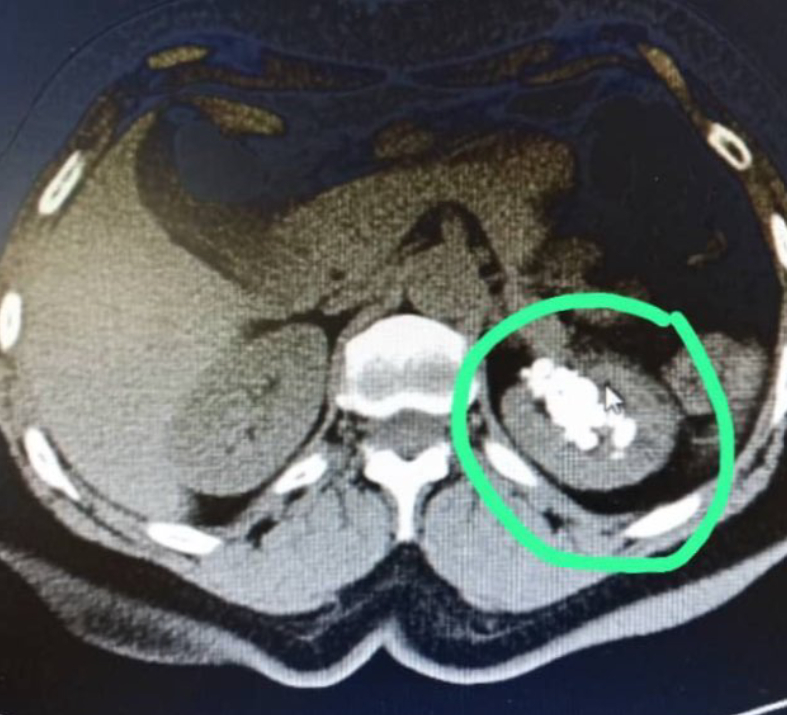

Gracias a estudios recientes, hemos determinado que mi mamá padece litiasis renal y ureteral (cálculos en los riñones y uréteres), además de un ureterocele izquierdo. Para que lo entiendan mejor, les pido que imaginen que su sistema urinario es como una red de tuberías. Los riñones son como las "fábricas" que producen la orina. Luego, unos tubos llamados uréteres la llevan desde los riñones hasta la vejiga, que es como un "tanque de almacenamiento" temporal. Finalmente, la orina sale del cuerpo por otro tubo llamado uretra. Ahora, un ureterocele es como un pequeño "globo" o "bolsa" que se forma al final de uno de esos tubos (el uréter), justo antes de que entre a la vejiga. Esto crea una especie de obstáculo. Mi mami tiene “piedras” en este sistema de tuberías, y el recorrido desde los riñones hasta la vejiga es un proceso bastante doloroso (porque las piedras suelen ser grandes en comparación con el pequeño tamaño del canal, haciendo un recorrido forzado). En la "bolsita" que se encuentra a la llegada de la vejiga, las piedras se van acumulando, haciendo una “pequeña parada” hasta que poco a poco algunas son expulsadas al orinar. Si no se trata a tiempo, las tuberías pueden obstruirse y el sistema colapsar.

Lo particular de su caso es que mi mamá posee un doble sistema de eliminación renal (es decir, funcionalmente tiene cuatro riñones), y solo uno de estos sistemas es el afectado. Esta condición única le ha permitido llevar una vida prácticamente normal a pesar de los cálculos y el dolor, con una vitalidad asombrosa que refleja diariamente en sus actividades. Sin embargo, los médicos han enfatizado que la cirugía es crucial para evitar complicaciones futuras.

- Urotac con contraste (Ver PDF: 3. Urotac con contraste - IDAT.pdf): Que reveló la litiasis en el sistema pielocalicial superior izquierdo y el doble sistema urétero-pielo-calicilar; costo $220.